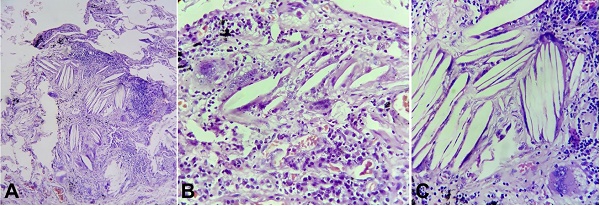

Hematoxylin and eosin stained microsections from this lung piece were examined under the light microscope and revealed congestion, interstitial lymphoplasmacytic infiltrate, interstitial fibrosis with a collection of foamy macrophages in alveolar spaces and cholesterol crystals surrounded by inflammatory reaction including occasional giant cells in almost all fields (Figure 1). These were surrounded by areas of fibrosis at few places that varied in intensity and completeness in these sites, thus fibrosis being the consequence rather than the cause of the process. Surrounding normal lung parenchyma could also be made out staining for mycobacteria and fungi were negative.

Apart from the clinical history, the presence of distinct histologic characteristics also helps in differentiation between the exogenous and endogenous forms. These include the detection of extracellular lipid material, the appearance of intracytoplasmic vacuoles (cholesterol clefts) in alveolar macrophages (as seen in our case), the distribution of macrophages in the lung tissue, and the physicochemical characteristics of the oil.12 It is also characterized by giant cell granulomatous reaction (hence also called lipid granulomatosis), chronic inflammation and alveolar and interstitial fibrosis.13